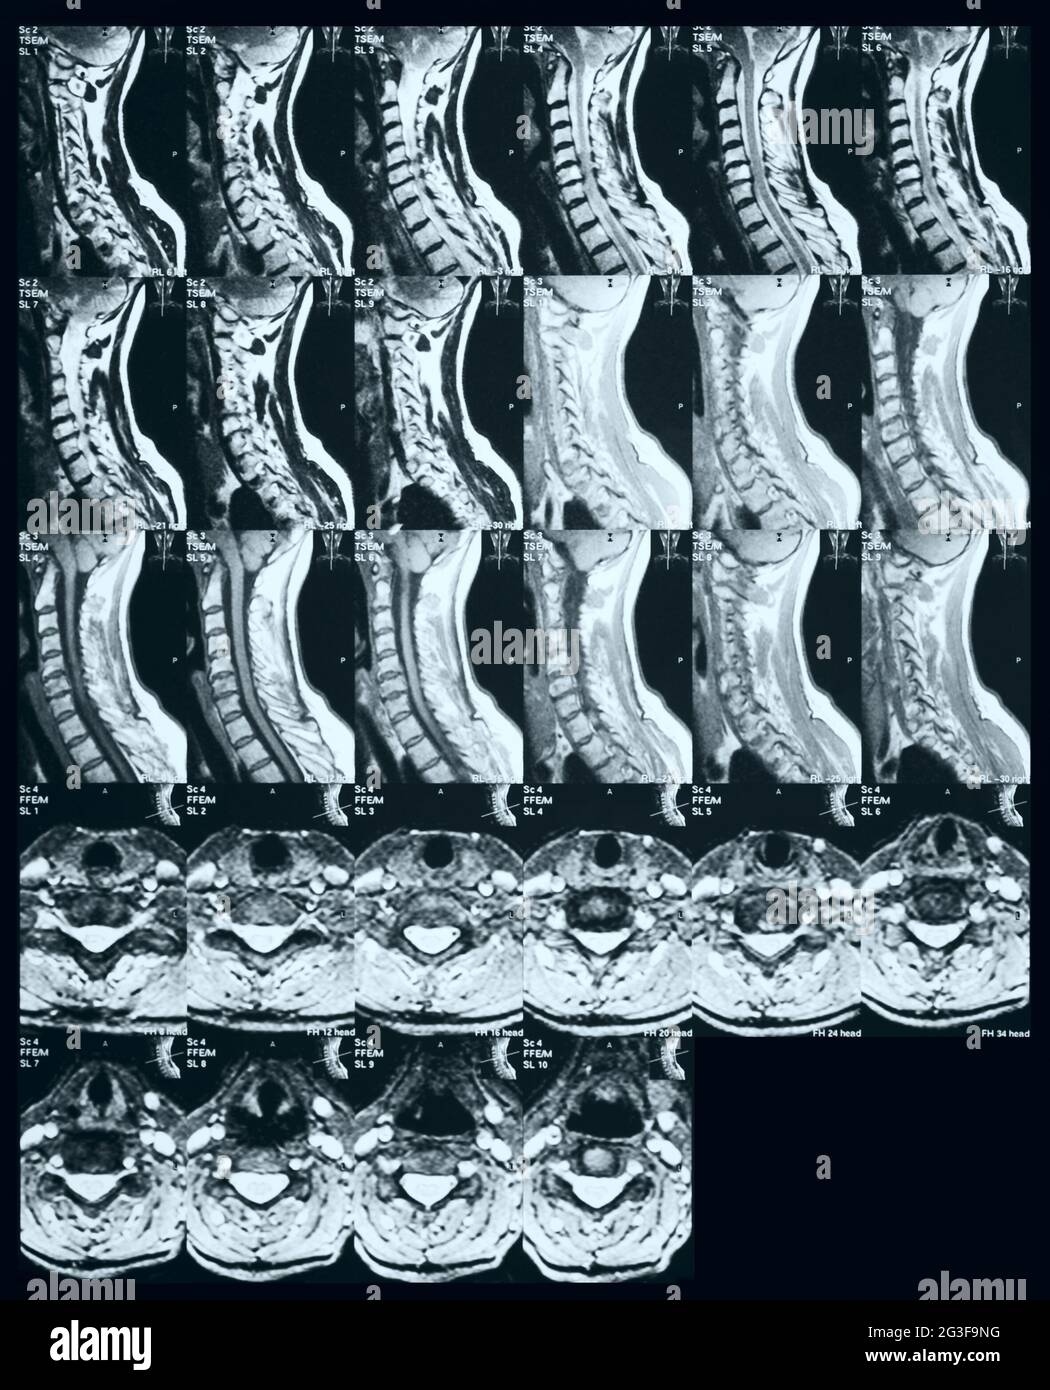

MRT Banque D'Imageshttps://www.alamyimages.fr/image-license-details/?v=1https://www.alamyimages.fr/mrt-image432440007.html

MRT Banque D'Imageshttps://www.alamyimages.fr/image-license-details/?v=1https://www.alamyimages.fr/mrt-image432440007.htmlRF2G3F9HY–MRT

MRT Banque D'Imageshttps://www.alamyimages.fr/image-license-details/?v=1https://www.alamyimages.fr/mrt-image432440108.html

MRT Banque D'Imageshttps://www.alamyimages.fr/image-license-details/?v=1https://www.alamyimages.fr/mrt-image432440108.htmlRF2G3F9NG–MRT